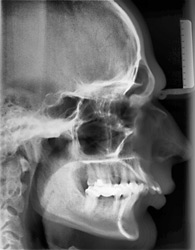

Kieferorthopädisch-kieferchirurgische Kombinationsbehandlungen

Wenn nicht nur die Zähne, sondern auch der Oberkiefer oder der Unterkiefer verändert werden müssen, so kann dies mit Spangen nur während der Wachstumsphasen gemacht werden.

Ist das Wachstum beendet, so kann diese Kieferveränderung nur operativ korrigiert werden.

Der Kieferorthopäde verschiebt die Zähne, der Kieferchirurg operiert den Kiefer. Anschließend sorgt der Kieferorthopäde wieder dafür, dass alles zusammenpasst.